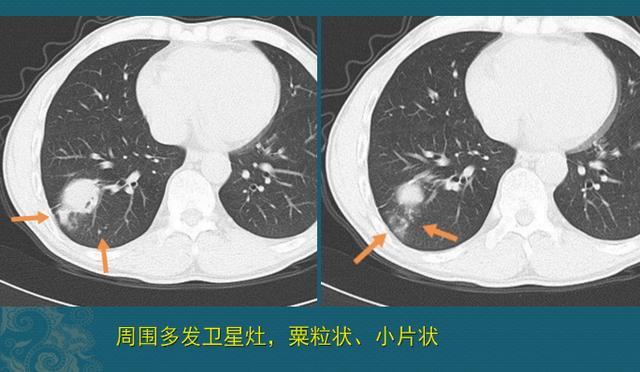

而肺结核则不然,它会繁殖,并且比癌细胞快很多倍,它适宜生长温度为37℃,正好是人体温度,增代时间大约为14-20小时。而且经气道吸入的结核菌原本就可以散布在多个角落,一起繁殖后代,造成病灶多发,所以我们看到结核球的周围经常有一些卫星灶,可以呈粟粒状、索条状、树芽征等多种表现,所以我们常说结核灶千变万化、无所不能。

下图是一位40多岁的男子,体检发现右肺肿块,周围有多发粟粒状、小斑片状影,提示结核球伴卫星灶,他比较紧张,选择手术切除,病例就是肺结核:

图片